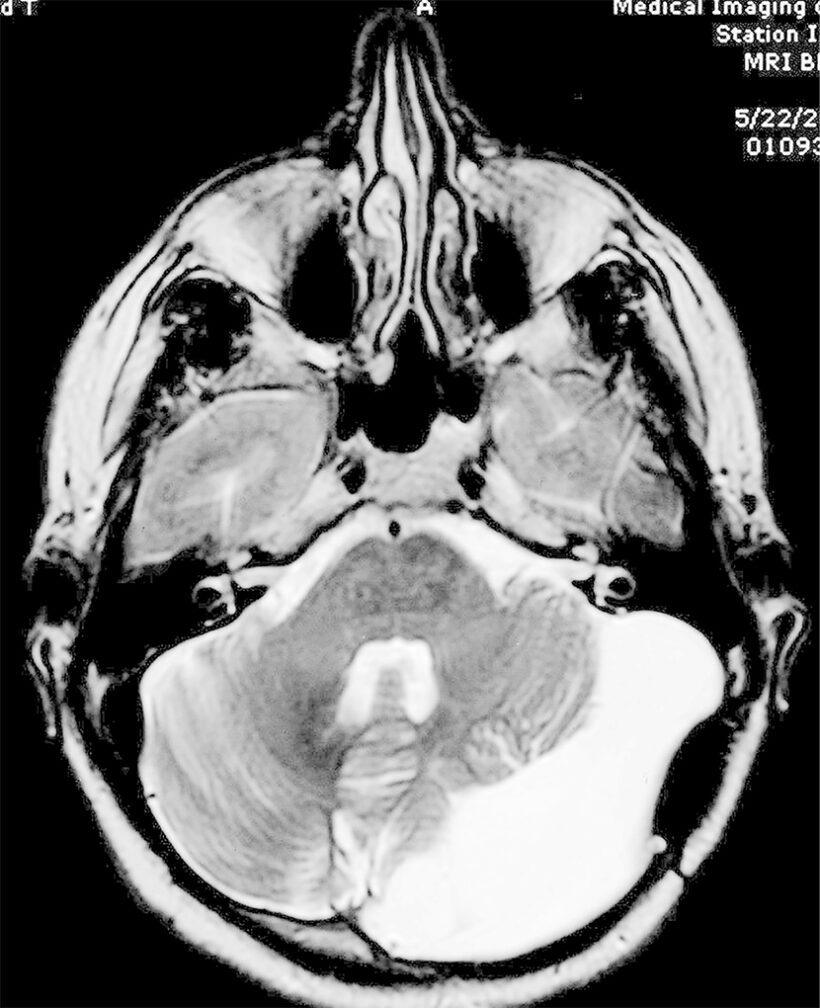

“We found the source of your headaches,” he said. “You have a very large arachnoid cyst on your left cerebellum. I’m talking BIG, the size of a fist. We need to remove it soon.”

Upon looking at Cyst 2.0, the neurosurgeon said when an obstruction has been there so long—my whole life, probably—the brain tissue just does not pop back into place once the cyst is gone. The empty space filled back with fluid, with cyst walls forming again to contain the goop.

Good call. When Dr. Mericle cracked open my head, he discovered the cyst had collapsed into a flat pancake-shaped mess of tissue gurgling with pockets of blood and reaching for my brain stem. It also tangled up already-agitated nerves in my neck and head.

I felt better after the third surgery; still, it was clear there were things I would just need to accept. The cyst, of course, popped right back into place, and the neuroworld decided to stop cracking me open and just treat the symptoms.

I get an MRI every few years, but the cyst has remained the same size and shape since it grew back after the third surgery. The stabbing eye pain shows up rarely, and the Fist of Ick on my cerebellum creates substantial balance issues. I often walk like a sailor spit out of a saloon at 3am.

My icky cyst on my left cerebellum is just a fistful of fluid that tinkers with my quality of life but not life itself. I have been to more than a handful of funerals for friends toppled by cancer in recent years, and it is jarring. These were mothers and fathers our age who took much better care of themselves than I do.